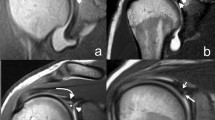

The reference slice (i.e., the slice used for morphological analysis) was selected by drawing a virtual plane at the great tuberosity, just above the proximal end of the bicipital groove. After a careful evaluation of the axial sequences, this seemed to be the one in which the point of passage from intra-to extra-articular portion of LHBT could be defined with greater precision (Fig. 1).

These landmarks were identified on the reference slice (Fig. 2):

-

A and A1: points beyond which the sphericity of the humeral head is outlined.

-

B: point below which the bicipital groove starts.

Once the landmarks were identified, a straight line was drawn connecting the landmark A with the landmark A1 (Fig. 3). Then, a second straight line was drawn (dashed in the figure), with a course parallel to the first line and tangent to the sphericity of the humeral head. The tangency point corresponds to the point of maximum convexity of the humeral head and, moreover, to the origin (O) of our reference system (Fig. 4). After identifying the origin (O) on the reference system, a Cartesian XY diagram was drawn (yellow lines in Fig. 4) with the X axis oriented along the major axis of the humeral head (Fig. 4). Subsequently, 4 orthogonal axes were drawn (1–4 green lines in Fig. 4) that intersected the previously identified landmarks A and B. Finally, a diagonal D (red line in Fig. 4) was drawn which served as a horizon in the morphological analysis.

Axial T2w-FFE sequence showing the straight line drawn to connect the landmark A with the landmark A1, and the second straight line drawn (dashed in the figure), with a course parallel to the first line and tangent to the sphericity of the humeral head. The tangency point corresponds to the point of maximum convexity of the humeral head and, moreover, to the origin (O) of our reference system

Axial T2w-FFE sequence showing the reference system used to identify the humeral head profile morphological variants. O represents the origin on the reference system; Cartesian XY (yellow lines) diagram is drawn with the X axis oriented along the major axis of the humeral head; 4 orthogonal axes (1–4 green lines) intersect the previously identified landmarks A and B; the diagonal D (red line) represents the horizon in the morphological analysis

Using this reference system, four possible main morphological variants were identified (Fig. 5): 1. flat shape; 2. convex shape; 3. spiculated shape; and 4. mixed morphology. A detailed description of the 4 morphological variants is shown in Table 3.